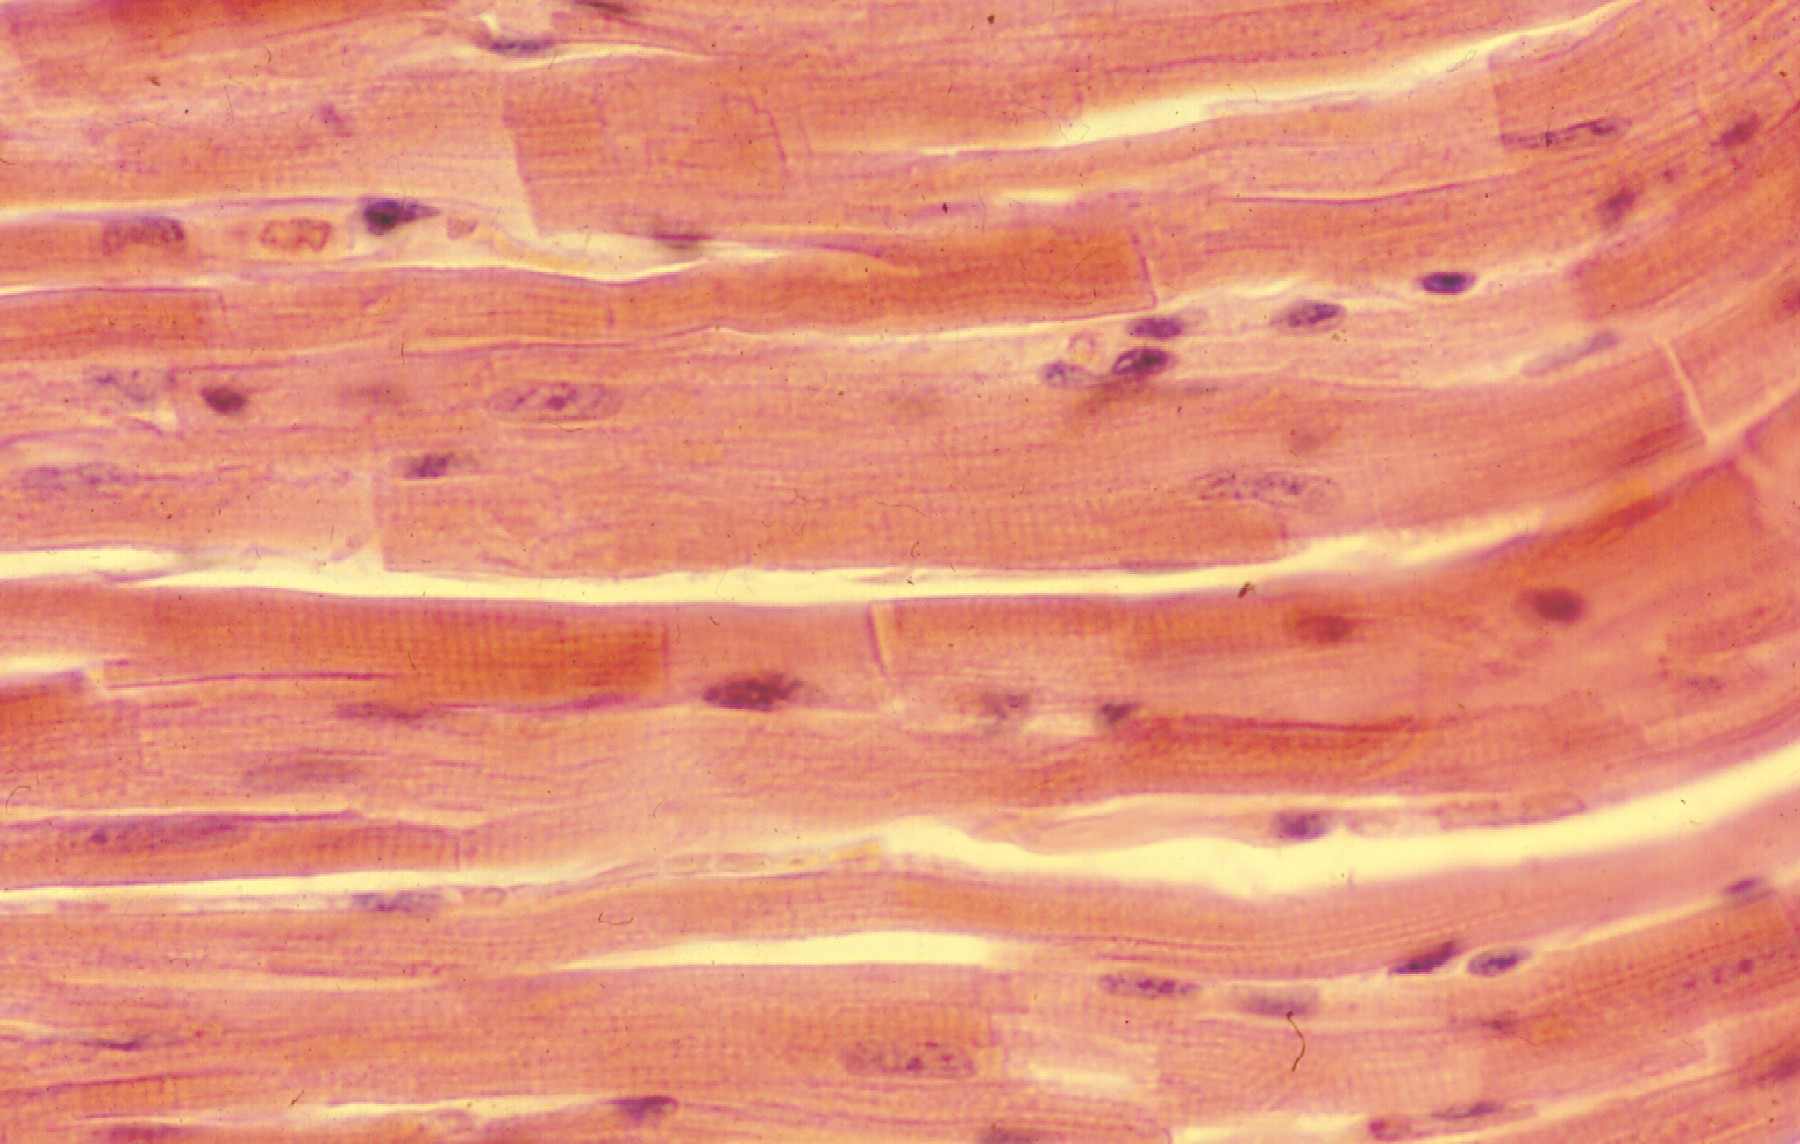

Il cuore è una struttura muscolare caratterizzata da cellule di piccole dimensioni che presentano un nucleo localizzato nella zona centrale della cellula stessa. Le cellule miocardiche sono organizzate in modo tale da garantire una veloce trasmissione dell’eccitazione: questa caratteristica è possibile in quanto le cellule sono in connessione con le strie scalariformi, ovvero zone del cuore in cui si ritrovano giunzioni comunicanti che consentono il rapido passaggio degli ioni coinvolti nella contrazione muscolare. La costante attività del cuore richiede molta energia e per sostenerne l’attività le cellule cardiache sono dotate di numerosi mitocondri deputati alla produzione energetica, ovvero di ATP. Nel cuore si possono inoltre ritrovare due tipi di tessuto, si parla pertanto di tessuto miocardico spugnoso che consente di muovere grandi volumi di sangue a basse pressioni, e tessuto miocardico compatto che permette invece di spostare piccoli volumi di sangue ad alta pressione. Una caratteristica fondamentale delle cellule muscolari cardiache è l’eccitabilità: quando vengono opportunamente stimolate, queste rispondono con una contrazione. Grazie alla presenza delle giunzioni comunicanti citate in precedenza, l’eccitazione si distribuisce velocemente a tutte le cellule adiacenti avendo come risultato finale la contrazione simultanea di grandi aree del cuore. L’attivazione del muscolo cardiaco è molto simile a quello del muscolo scheletrico, nella contrazione vengono infatti coinvolti gli stessi ioni. La durata della contrazione risulta essere però più lunga nel muscolo cardiaco nel momento in cui il passaggio di ioni dall’interno all’esterno della cellula e viceversa, risulta essere meno immediato.

Mentre uccelli e mammiferi presentano quattro camere cardiache (due atri posti sopra due ventricoli) separati verticalmente dal setto cardiaco e delimitati orizzontalmente da valvole, i teleostei e gli elasmobranchi presentano un cuore con un’organizzazione a S. Nel caso degli elasmobranchi le camere sono rappresentate da un seno venoso, un atrio, un ventricolo e un cono arterioso. Come negli omeotermi il passaggio di sangue è regolato da valvole che in questo caso sono poste tra seno venoso e atrio, atrio e ventricolo, e infine vi è una numerosa serie di valvole a livello del cono arterioso. Nei teleostei la struttura generale è molto simile, l’ultima camera in questo caso prende però il nome di bulbo arterioso, che a differenza del cono venoso non presenta valvole, ed è il risultato di una modificazione del tratto iniziale dell’aorta. Sia nei teleostei che negli elasmobranchi, il ventricolo è la camera cardiaca in grado di sviluppare la maggior forza propulsiva grazie a una parete muscolare molto spessa che è costituita da tessuto muscolare cardiaco compatto e spugnoso. Un’altra grande differenza è da ritrovarsi nella conformazione delle cellule cardiache che in questi animali si presentano allungate e sottili. Per quanto riguarda la contrazione cardiaca, in teleostei ed elasmobranchi è innescata da cellule pacemaker localizzate nel seno venoso, pertanto a partire dal nodo del seno viene generato un potenziale d’azione che si propaga ordinatamente alle cellule cardiache grazie alla presenza di giunzioni comunicanti che consentono di attivare in sequenza le diverse camere cardiache.